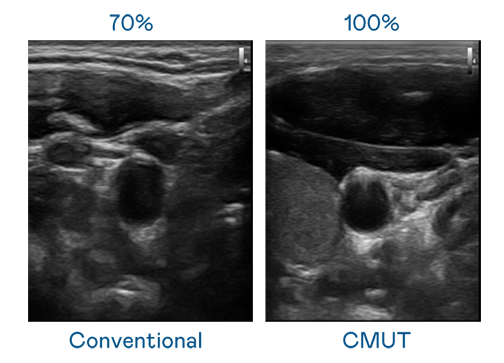

CMUT 技术是一种用电容式微机电元件来产生超音波讯号的技术。与传统 PZT 压电式技术相比,CMUT 频宽增加 30%,更宽频的超音波讯号让影像解析度大幅提升,是实现高影像品质医疗超音波扫描、促进精准医疗发展的关键技术。

大频宽带来超清晰影像

超音波影像的解析度高低,首先取决于探头能发出的讯号频宽。AG公司 CMUT 可提供高清晰的超音波讯号,提供高频宽、高灵敏度、影像纹理细节更高的超音波影像,协助医护人员缩短影像判读时间及利用精准的医疗影像进行诊断。